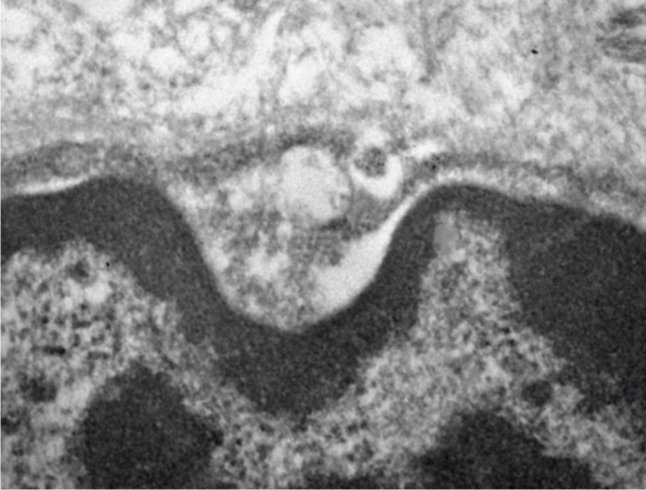

Já por meio de marcações imuno-histoquímicas – em que é colocado um corante em uma molécula que se gruda no vírus e nos receptores –, foi possível observar a presença do vírus in situ, no interior dos tecidos. E, por meio de microscopia eletrônica, foi detectada não só a presença, mas também o vírus se replicando nas células e identificado o tipo de organela que ele utiliza para essa finalidade.

“Observamos vários vírus aglomerados nas células das glândulas salivares – um indicativo de que estão se replicando em seu interior. Não estavam presentes nessas células passivamente”, afirma Matuck.